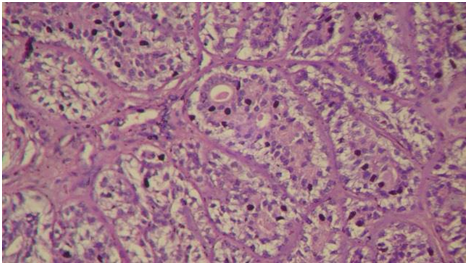

Pyriform sinus tumors account for 70% of cancers originating in the hypopharynx. Tumors originating from the medial wall of the pyriform sinus behave similarly to supraglottic tumors arising from the aryepiglottic folds, and it is often difficult to know the true origin of some of these lesions.7 The most common site of epithelial myoepithelial carcinoma is the parotid gland. In the literature, only 4 cases have been reported to occur in the larynx and only one case has been reported in the hypopharynx. Histologically, epithelial myoepithelial carcinoma is characterized by two types of cells arranged in well-defned tubules; epithelial cells in the inner layer and myoepithelial cells in the outer layer.4 The nodal and distant metastasis rates are low.8 These tumors arise from the subepithelial mucous glands in the larynx. Usually, any hypopharyngeal tumor presents with dysphagia. In our patient, the main presenting symptom was dyspnea, mostly probably exacerbated by the morbid obesity that the patient suffered from(Figure 2).9,10

Figure 2 Tumor characterized with Biphasic, two types of cells: An outer layer of myoepithelial cells with a clear cytoplasm and an inner lining of eosinophilic cuboidal epithelial cells.